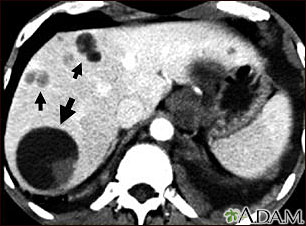

This upper abdominal CT scan shows multiple cysts in the liver, caused by dog tapeworm (echinococcus). Note the large circular cyst (seen on the left side of the screen) and multiple smaller cysts throughout the liver.